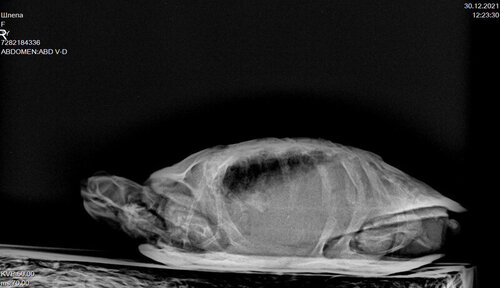

Врач Шевченко Матвей Олегович, вет.клиника Прайд: сделал рентген, сказал, что что-то есть в желудке и что-то давит на лёгкие, заметил розоватый цвет на лапах и пластрон - сказал, что возможно воспаление или проблемы с почками

7282184336_1.thumb.JPG.d04b396017daf9699fd013ff158ea415.JPG7282184336_2.thumb.JPG.daf96f8221ee11b4a2738eae8e3638c0.JPG

В Вашем случае нужно определять требуется операция или нет, есть непроходимость или трава движется по жкт. По-хорошему Вам должны были делать рентген с контрастом и интервальные снимки, а не гадать что там пережимает лёгкие. Потому что рвота эспумизаном это либо Вы неправильно вводите катетер и не попадаете в желудок, либо движения по жкт нет и эспумизану просто некуда деваться.

@moth Черепашка покакала, скушала один кусочек Серы и поклевала сепию. Свозила в Котонаи, там ее прощупали, сделали рентген и взяли кровь на биохимический анализ. В кишечнике есть инородные кусочки, но сказали, что непроходимости нет. Вкололи Элеовит 0,1 мл. Сказали пока ничего не делать и ждать анализов крови